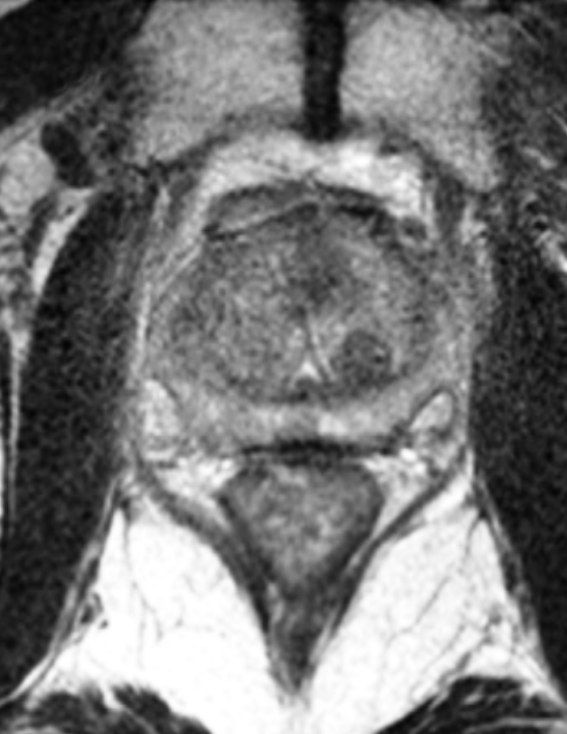

SpaceOAR provides an 1.3cm space between the prostate and rectum for prostate cancer radiation patients to help reduce radiation complications.

SpaceOAR Hydrogel is an absorbable hydrogel that temporarily creates space between the prostate and rectum, designed to reduce the radiation dose delivered to the rectum during prostate cancer radiation therapy.1